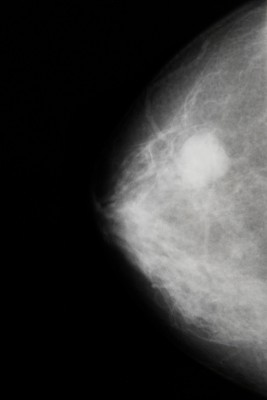

높은 골밀도 및 유방암 골밀도 에 대한 가장 중요한 사실 중 하나는 논의에서 눈에 띄지 않았지만 중년 및 노년 여성의 골밀도가 정상보다 높으면, 실제로 유방암 위험이 200% -300% 증가한다는 것입니다.

이것은 Lancet, JAMA, NCI와 같은 세계에서 가장 존경받고 권위 있는 저널에 발표된 연구에 따른 것입니다. (아래 인용 참조). 높은 골밀도가 유방암의 위험을 크게 증가시킨다는 것은 적어도 15년 동안 알려져 왔습니다. — 특히 악성 유방암 — 이 문제는 주류 여성 건강 옹호 단체에서 설명하는 선전과 모순되기 때문에 거의 또는 전혀 주의를 기울이지 않았습니다.

유방암 인식 프로그램은 "조기 발견"의 한 형태로 X선 기반 유방 검진에 중점을 두고 있으며, 국립 골다공증 재단의 전체 플랫폼은 골다공증 예방을 위한 골밀도 증가가 삶의 질과 수명 향상으로 이어진다는 믿음을 설명하는 데 기반을 두고 있습니다. 여성들을위한. 그러나 연구는 사라지지 않으며 결국 이러한 조직은 이를 인정해야 하며 그렇지 않으면 신뢰성을 잃을 위험이 있습니다.

High bone-mass density as a marker for breast cancer in post-menopausal women.